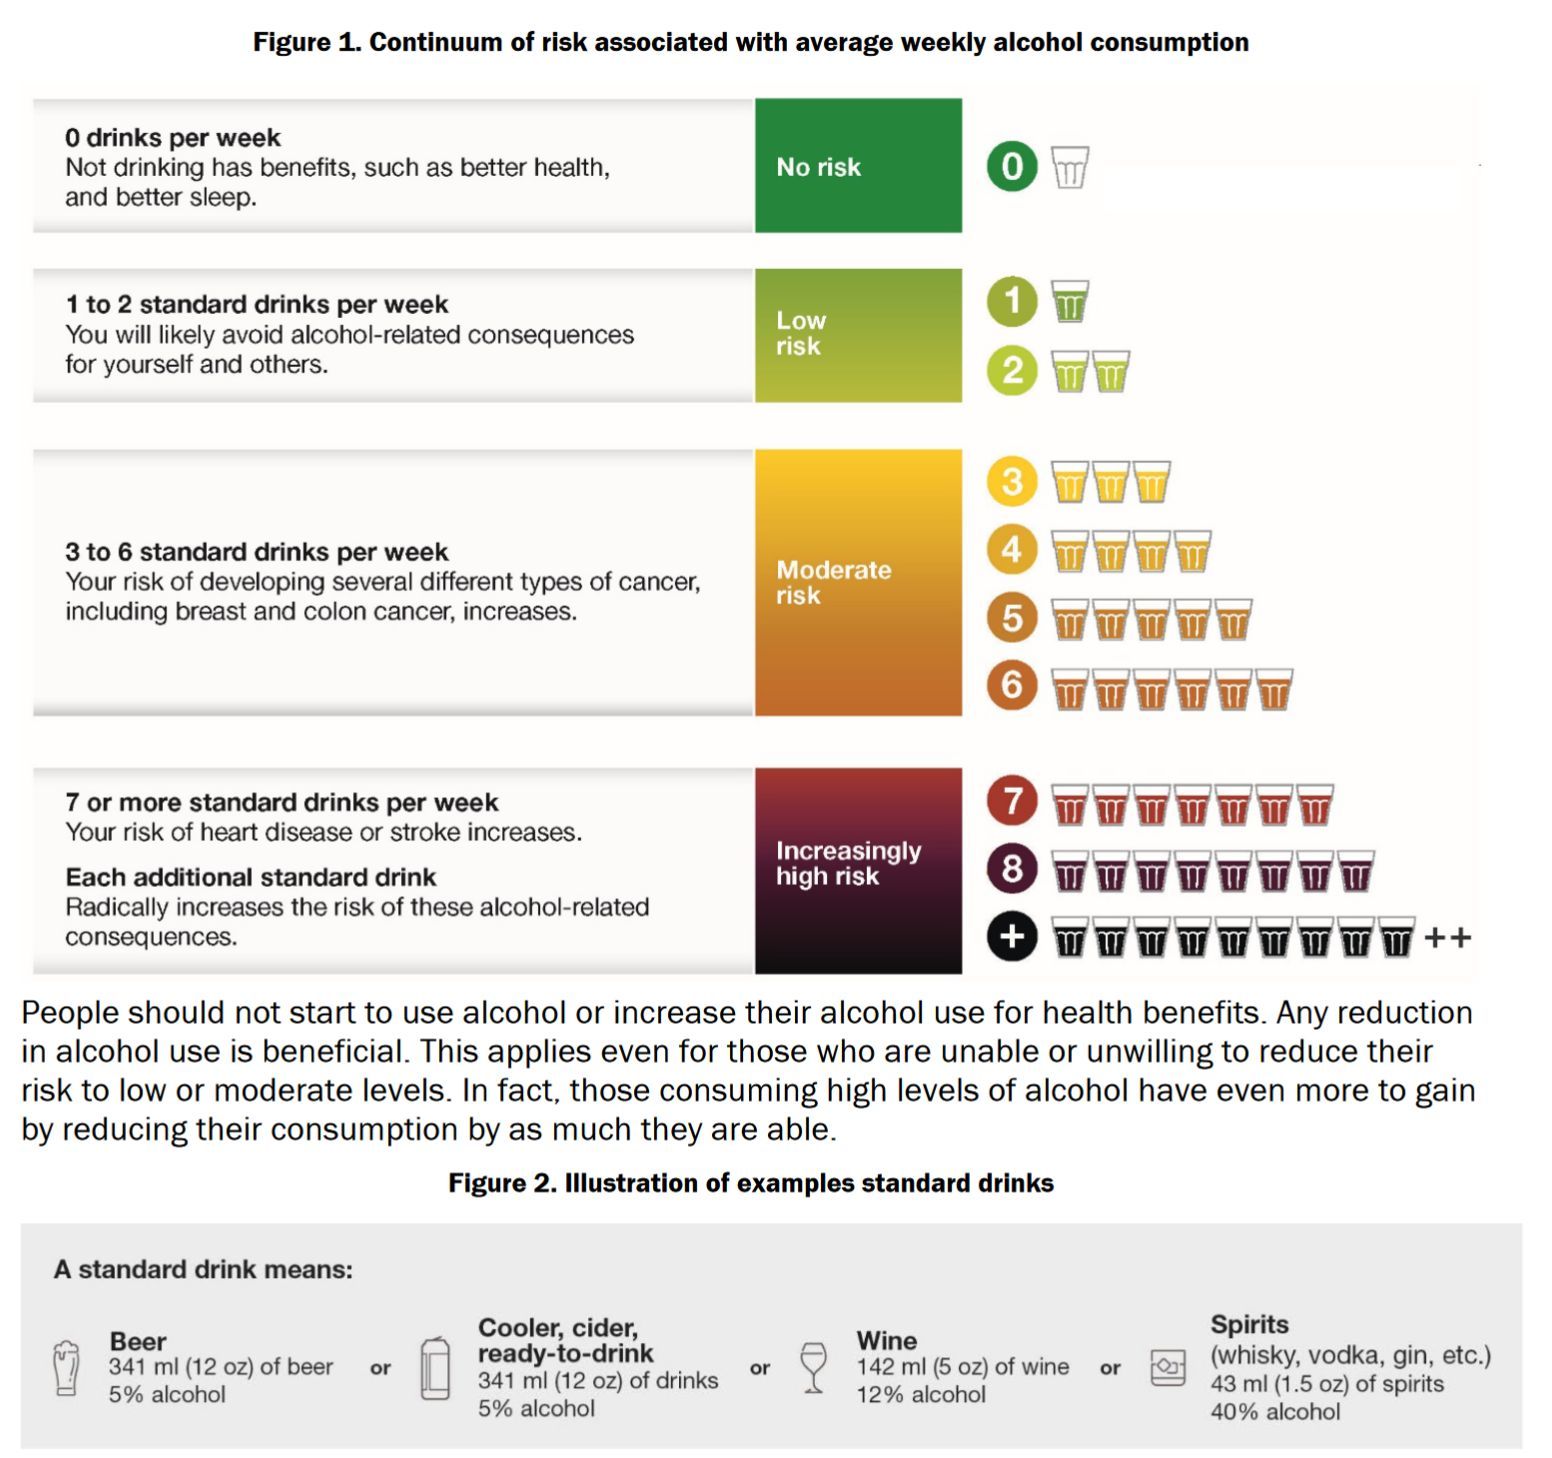

| Subject | "한주에 맥주 두잔" 캐나다, 자국민에 '사실상 금주' 권고 |

https://www.yna.co.kr/view/AKR20230119056800009 https://ccsa.ca/sites/default/files/2023-01/Canada%27s%20Guidance%20on%20Alcohol%20and%20Health%20Final%20Report_l.pdf https://en.wikipedia.org/wiki/Standard_drink 2011년 권고에 비해서 많이 강화되었군요. 한글 기사의 주 15회, 주 10회 얘기는 스탠다드 드링크 기준입니다. 나라마다 스탠다드 드링크에 차이가 있습니다. 0